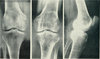

בדיקת צפיפות העצם היא קצרה, פשוטה ולא פולשנית, וחשובה ביותר לאבחון דלדול העצם ולמניעת שברי אוסטאופורוזיס. מהי מחלת האוסטאופורוזיס? מיהי אוכלוסיית הסיכון? וגם: מידע על בדיקת צפיפות עצם. לפרטים נוספים

אצל נשים בגיל הבלות, עקב הפסקת ייצור הורמון האסטרוגן החיוני לשמירה על העצמות, מתחיל תהליך מואץ של אבדן מסת עצם. הירידה החדה בצפיפות העצם מעלה את הסיכון למחלת האוסטיאופורוזיס אשר גורמת להיחלשות העצמות ולנטייה לשברים, בפרט באזור אגן הירכיים, פרק כף היד ועמוד השדרה. לפרטים נוספים

סידן הוא המינרל השכיח מבין כל המינרלים בגופנו. הוא מהווה מרכיב חיוני בשלד (99% ממנו מצוי בעצמות ובשינויים) ובעל תפקיד משמעותי גם בפעילותן התקינה של מערכות נוספות הגוף, בהן מערכת השרירים, מערכת העצבים, הלב ועוד. בריחת סידן היא תופעה שבה מסיבות שונות יורדת רמת הסידן בגוף, וחל תהליך מואץ של פירוק העצם. תהליך זה מוביל לדלדול עצם, ובשמו הלועזי אוסטאופורוזיס - מצב שבו רקמת העצם מאבדת מצפיפותה ודופן העצם מאבד מחוזקו. טיפול בבריחת סידן לאחר הופעת התסמינים הוא מוגבל. מכאן חשיבות המניעה,ויפה שעה אחת קודם. לפרטים נוספים